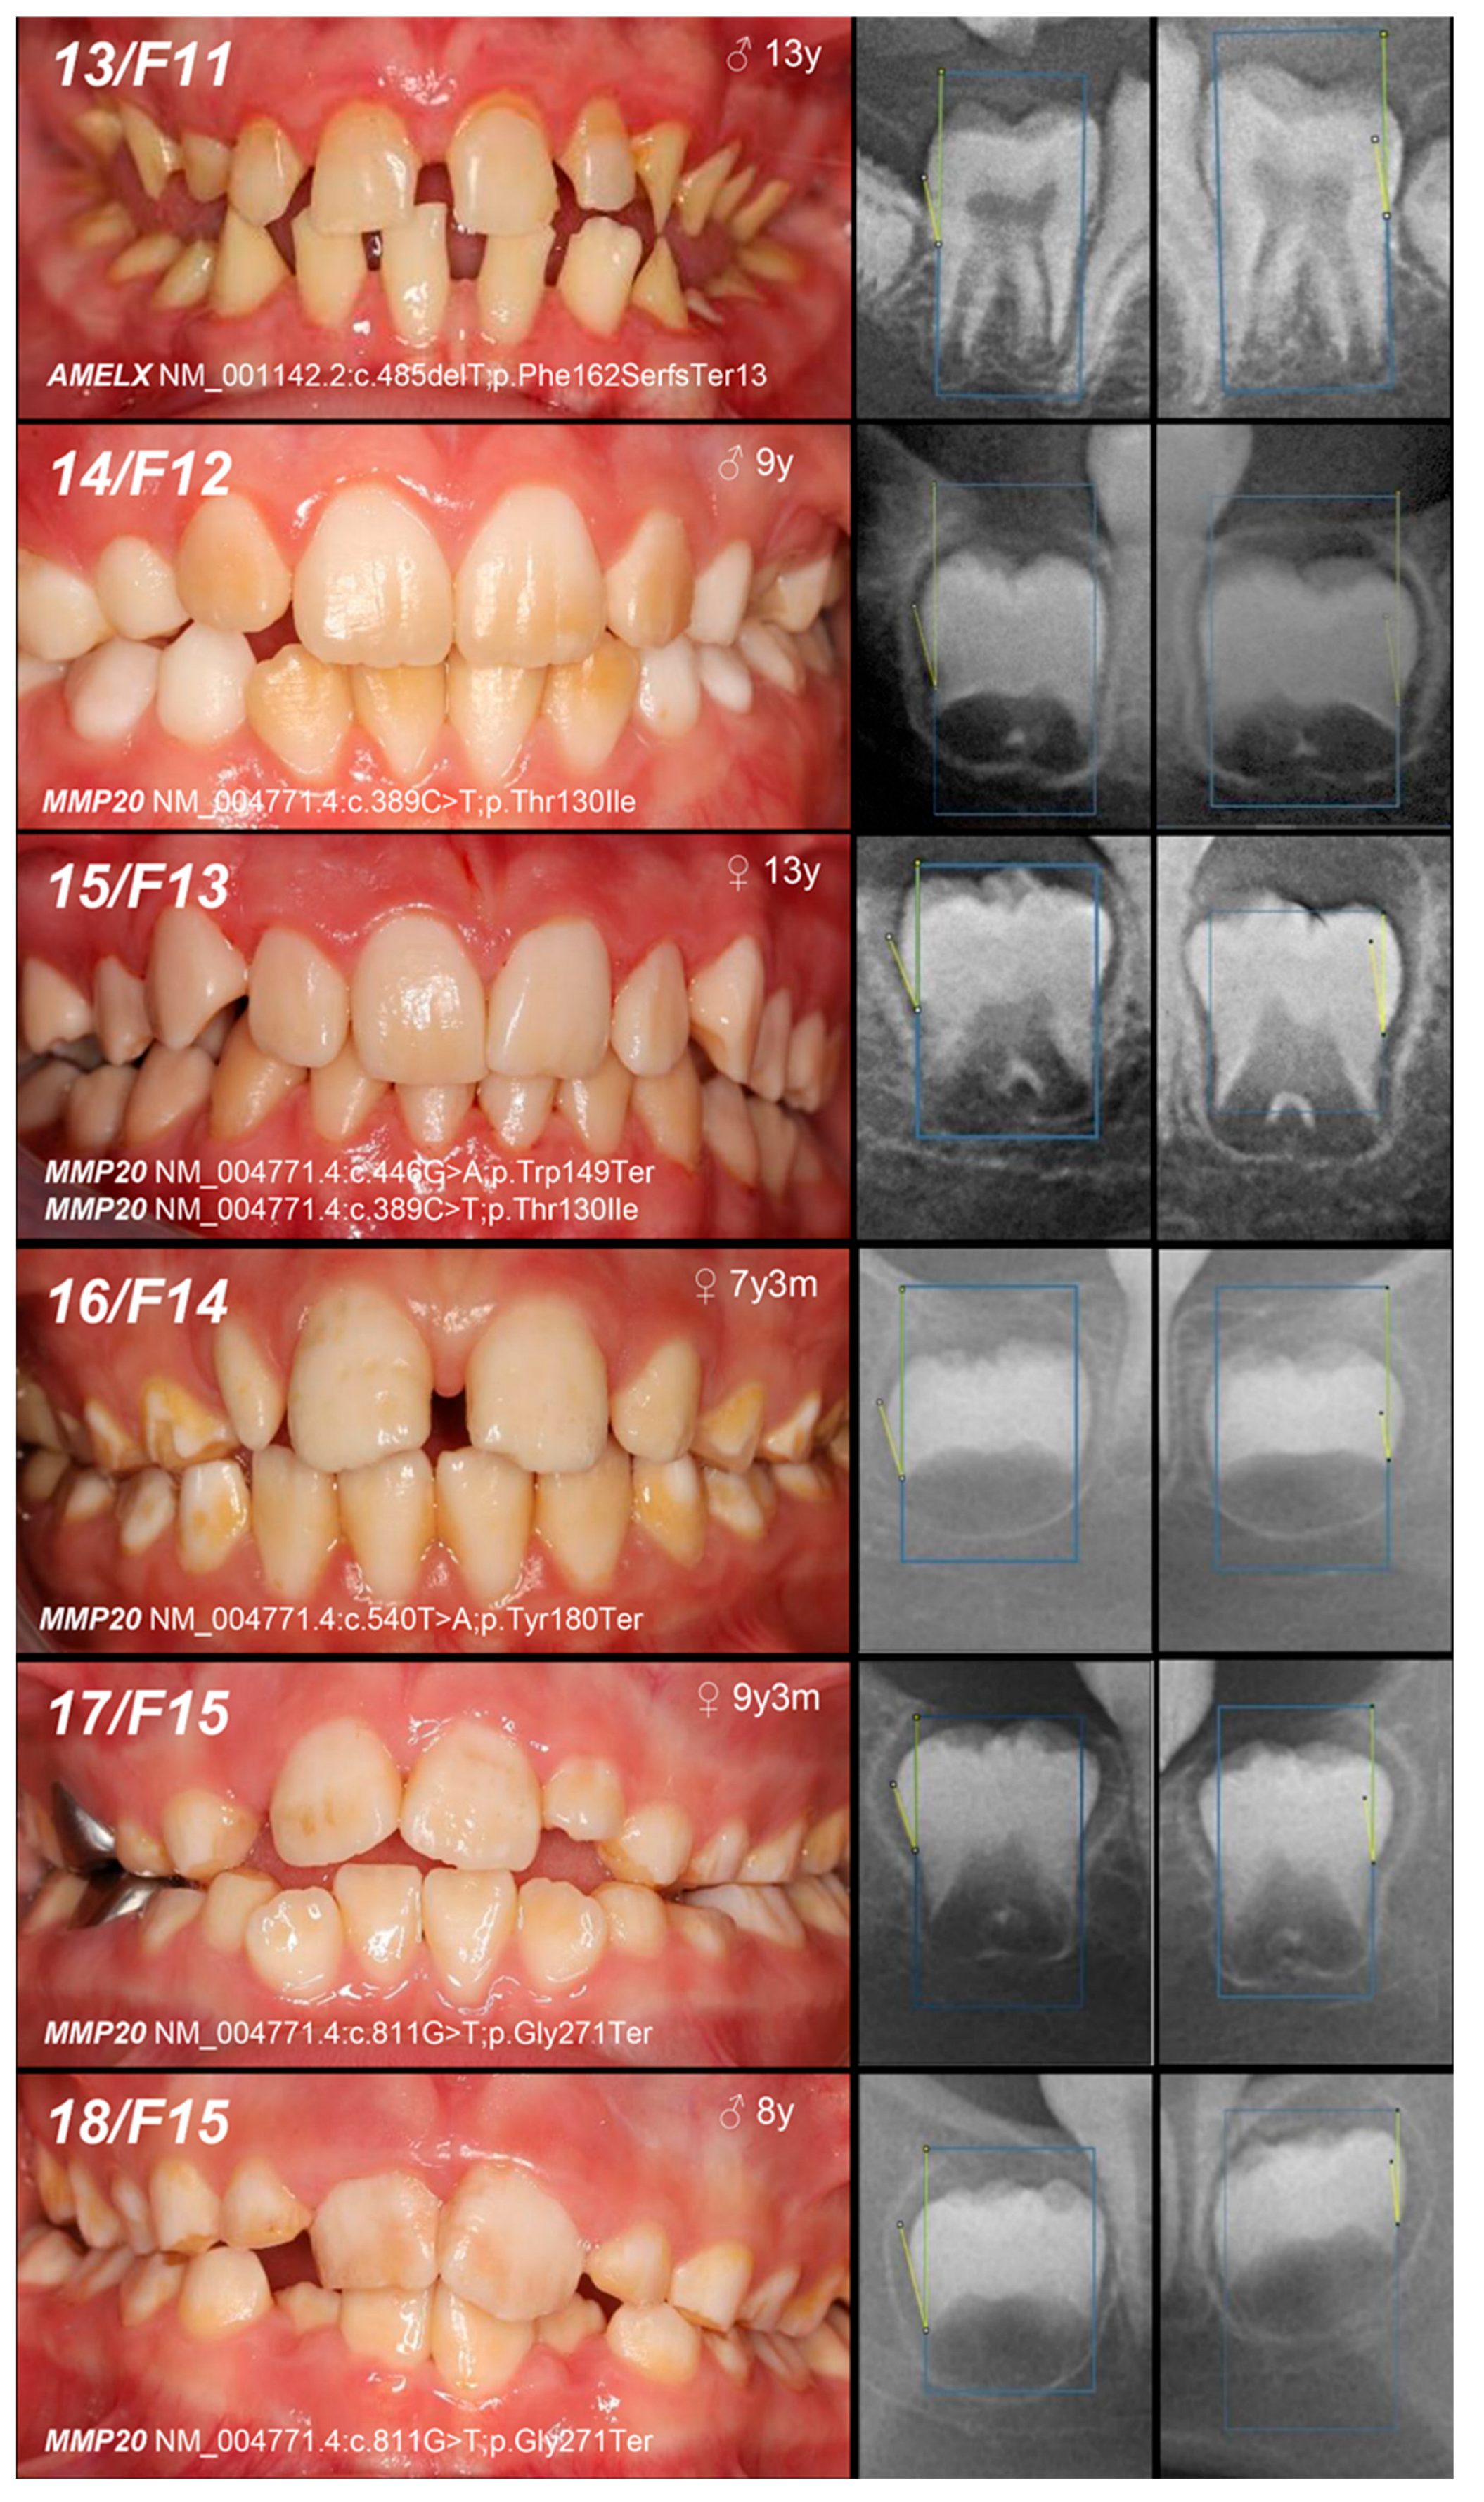

| 13, F11 | Hypoplastic (heterogeneity) | IE, XLD, AMELX | c.485delT | 0/− | p.Phe162SerfsTer13 | novel | MoS (A) Fa (NA) | likely pathogenic (PVS1:very strong, PM2:moderate) |

| 14, F12 | Hypomineralized (pigmented hypomature) | IIA2, AR, MMP20 | c.389C>T | −/− | p.Thr130Ile | [27] | MoFa (UC) | likely pathogenic (PP5: strong, PM2: moderate) GnomAD: 0.001747 |

| 15, F13 | +/− | Mo (U) Fa (NA) | ||||||

| and c.446G>A | +/− | and p.Trp149Ter | novel | likely pathogenic (PVS1:very strong, PM2:moderate) GnomAD: 0.00000398 |

| 16, F14 | Hypomineralized (pigmented hypomature) | IIA2, AR, MMP20 | c.540T>A | +/− | p.Tyr180Ter | [28] | Mo (UC) Fa (U) | likely pathogenic (PVS1: very strong, PM2: moderate) GnomAD: 0.00000707 |

| 17, 18, F15 | c.811G>T | +/− | p.Gly271Ter | novel | Mo (AC) Fa (U) | likely pathogenic (PVS1: very strong, PM2: moderate) | ||

| +/− | ||||||||

| 19, F16 | +/− | Mo (UC) Fa (U) | ||||||

| 20, F17 | Hypoplastic (pitted) | IA, AD, LAMB3 | c.-132T>C | +/− | / | novel | Mo (AC) Fa (U) | VUS (PM2: moderate, BP7: supporting) |